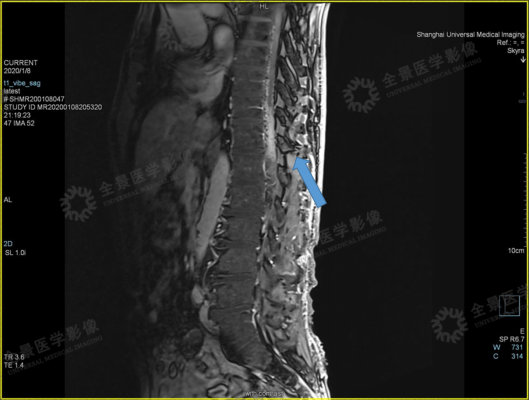

案例二

男,58 岁。右下肢乏力逐渐加重 1 年,双下肢无力 1 月。

2020 年 1 月 8 日,肌电图示:腰骶段脊髓神经损害。

DSA 结果:硬脊膜动静脉瘘。